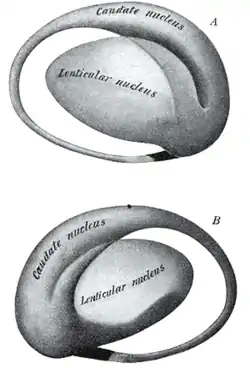

Together with the putamen, the caudate forms the dorsal striatum, which is considered a single functional structure; anatomically, it is separated by a large white matter tract, the internal capsule, so it is sometimes also referred to as two structures: the medial dorsal striatum (the caudate) and the lateral dorsal striatum (the putamen). In this vein, the two are functionally distinct not as a result of structural differences, but merely due to the topographical distribution of function.

The caudate nuclei are located near the center of the brain, sitting astride the thalamus. There is a caudate nucleus within each hemisphere of the brain. Individually, they resemble a C-shape structure with a wider "head" (caput in Latin) at the front, tapering to a "body" (corpus) and a "tail" (cauda). Sometimes a part of the caudate nucleus is referred to as the "knee" (genu).[7] The caudate head receives its blood supply from the lenticulostriate artery while the tail of the caudate receives its blood supply from the anterior choroidal artery.[8]

The head and body of the caudate nucleus form part of the floor of the anterior horn of the lateral ventricle. After the body travels briefly towards the back of the head, the tail curves back toward the anterior, forming the roof of the inferior horn of the lateral ventricle. This means that a coronal (on a plane parallel to the face) section that cuts through the tail will also cross the body and head of the caudate nucleus.